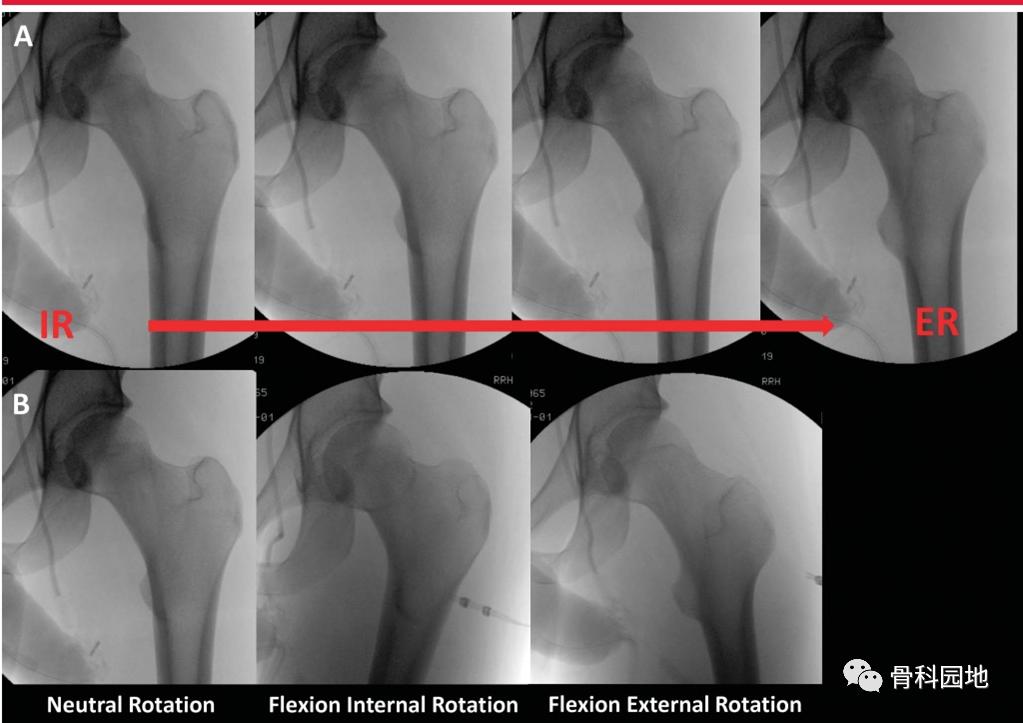

为了评估骨折固定期间的透视视图,必须了解完整股骨的近端股骨关系,以及它们如何随透视光束位置、腿部位置和正常解剖变异而变化。股骨近端图像显示股骨粗隆尖与股骨头中心的标准关系,当股骨近端向外旋转时,股骨颈轴角度增加,股骨颈似乎变短(下图)。

x线片显示同一髋从内旋(IR)到外旋(ER)的AP透视图像。注意髋关节从IR到ER的距骨轮廓的变化。当颈干角从屈曲/IR到屈曲/外旋时,注意颈干角角度的外观。

同样,髋关节屈伸可以显著改变颈轴角度的透视图。在Bhashyam等人的研究中,髋关节屈伸和旋转对NSA的测量有协同效应,当髋关节屈伸在中立位10°以内时,测量误差最小。因为受影响的髋关节倾向于屈曲和内旋,这会给人内翻增加的错觉。